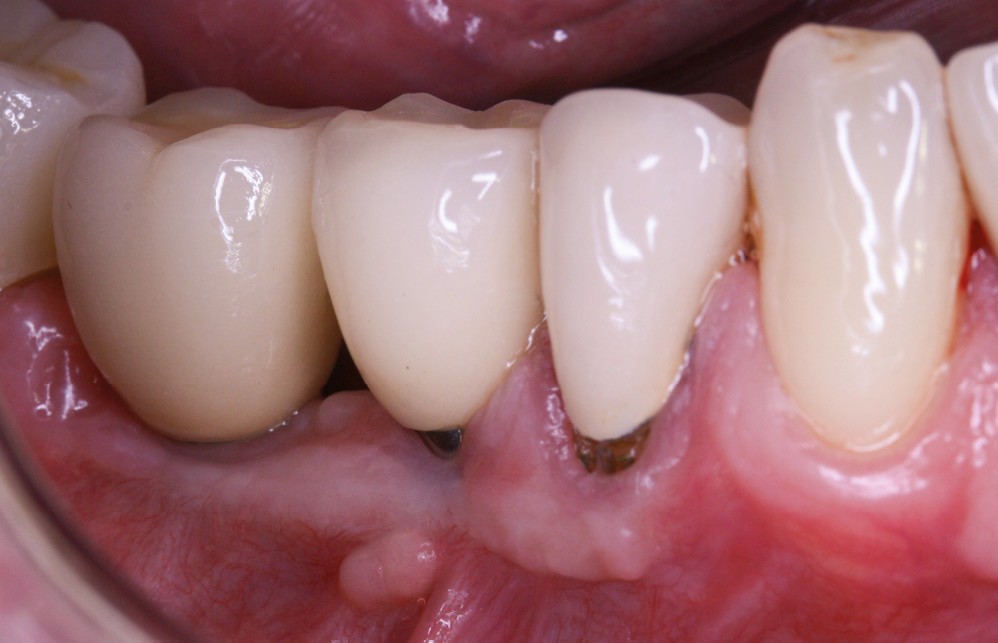

La greffe épithélio-conjonctive (GEC) [7, 8] consiste au remplacement du tissu parodontal existant par un greffon épithélio-conjonctif dont l’indication principale est l’augmentation en hauteur et en épaisseur du tissu kératinisé (fig. 2). Elle peut aussi être utilisée dans le recouvrement radiculaire (avec des résultats en termes de recouvrement inférieurs à ceux des techniques de greffe de conjonctif enfouie), l’aménagement des crêtes édentées, l’aménagement péri-implantaires [9, 10] (fig. 3), ou en association avec un traitement ortho-parodontal [11]. Le principal défaut de cette technique est son aspect inesthétique ; elle sera donc réservée à des zones non visibles comme les incisives mandibulaires ou les zones postérieures.